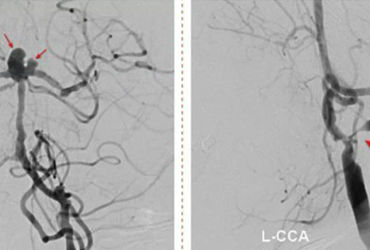

Đột quỵ đặc biệt nguy hiểm: Cuộc chiến với nhồi máu não và nguy cơ vỡ túi phình

Khám phá cuộc chiến đầy cam go của người phụ nữ đối diện với 2 loại đột quỵ đặc biệt nguy hiểm: nhồi máu não và nguy cơ vỡ túi phình. Hãy cùng tìm hiểu về quá trình can thiệp và hồi phục của bệnh nhân...